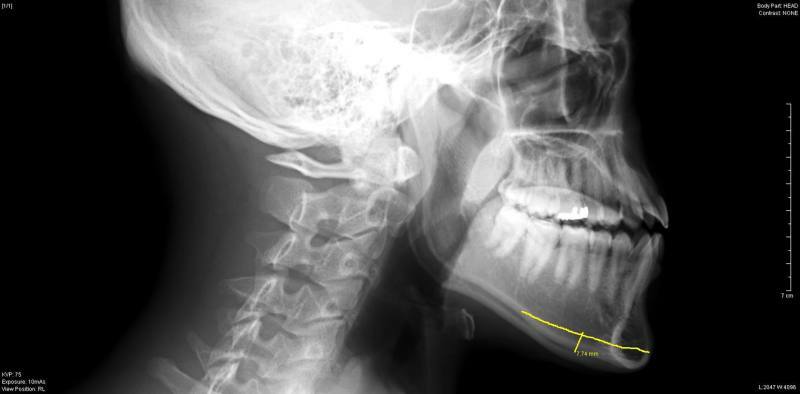

頭蓋側面のレントゲン写真では、

下顎骨の中央から、

先端にかけて幅が広くなっているのがわかります

男性の骨は、

硬く厚いため、

骨切りには時間がかかりましたが、

無事写真の通り、

切り出すことができました。

(骨片の左側が短いのは、

骨が途中で割れてしまったためで、追加切除しています。)

もちろん、オトガイ神経は傷つけていません